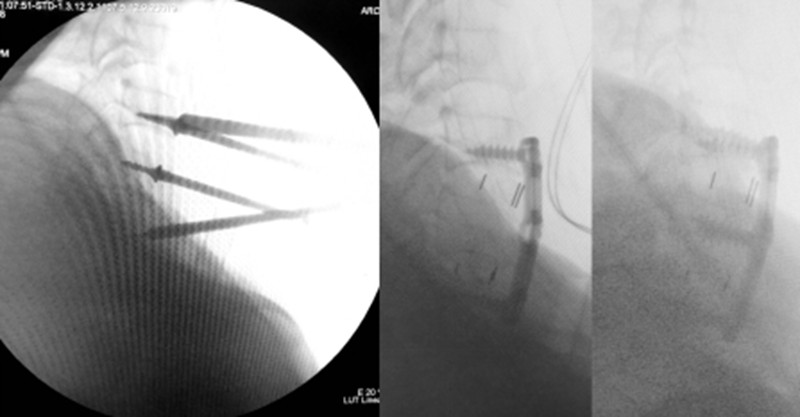

此次手术在国务院特殊津贴专家、骨科主任医师李玉伟教授带领下实施。手术摒弃了常规的牵引等待环节,直接进入手术室。团队通过单纯的前路切口,先切除了导致脊髓压迫的突出椎间盘及骨折碎片,实现了脊髓的即时减压,为后续操作创造了安全空间。紧接着,团队运用“单侧偏心撑开”联合后凸撑开撬拨技术,成功完成了脱位关节的复位。

该技术路径的核心思路在于优先解除脊髓压迫,避免在复位过程中可能对已受损神经造成的二次损伤风险。整个手术过程体现了微创理念,力求操作精准、高效,减少组织创伤和术中出血,缩短手术时间。